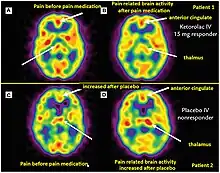

Brain perfusion SPECT shows dental pain patients with analgesia (top row) versus placebo (bottom row).

Single-photon emission computed tomography (SPECT) is employed in theranostics, using gamma rays emitted by a radiotracer to generate three-dimensional images of the body. SPECT imaging involves the injection of a radiotracer that emits single photons, which are detected by a gamma camera rotating around the person undergoing imaging.[6]

SPECT provides functional and anatomical information, allowing the assessment of organ structure, blood flow, and specific molecular targets. It is useful in evaluating diseases that involve altered blood flow or specific receptor expression. For example, SPECT imaging with technetium-99m (Tc-99m) radiopharmaceuticals may be able to assess myocardial perfusion and identify areas of ischemia or infarction in patients with cardiovascular diseases.[12]

SPECT imaging helps in identifying disease localization, staging, and assessing the response to therapy. Moreover, SPECT imaging is employed in targeted radionuclide therapy, where the same radiotracer used for diagnostic imaging can be used to deliver therapeutic doses of radiation to the diseased tissue.[12]